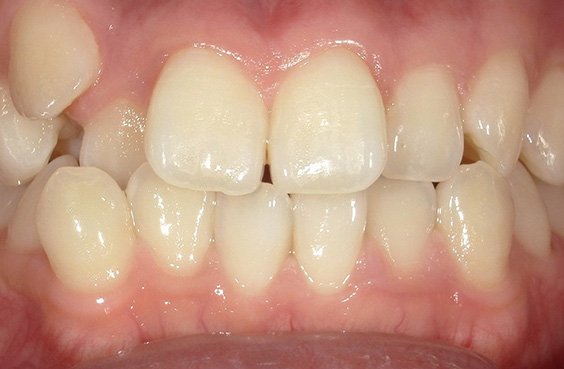

- 症例1

治療期間 4カ月

治療費 23.1万円(月額1,925円~)

※上顎前歯部、下顎前歯部の叢生をマウスピース型矯正装置で改善したケース。矯正治療上のリスクとして、治療中の虫歯、歯根吸収、歯肉炎 ・歯周炎の発生などが考えられる。